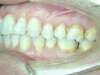

Vues avant le traitement

Vues après le traitement